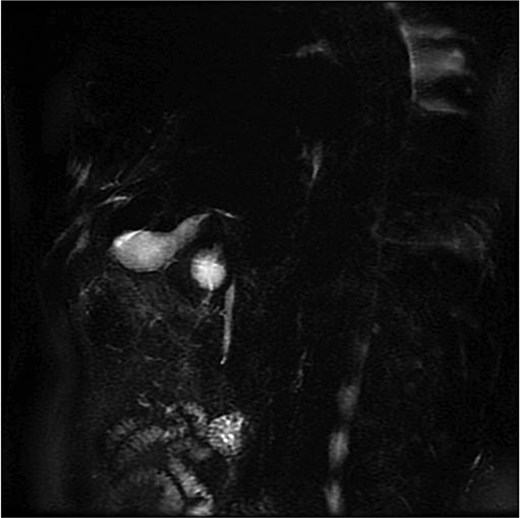

Lab tests showed leukocytosis (15.2 × 103/μl), thrombocytopenia (95.8 × 103/μl), elevated CRP (25.22 mg/dl), procalcitonin (4.49 ng/ml), and total bilirubin (3.5 mg/dl). Liver function was otherwise normal. Ultrasound revealed lithiasic cholecystitis with hydrocholecystosis. Computed tomography (CT) failed to detect duplication (Fig. 1a and b). MRCP confirmed H-type duplicated gallbladder with two independent cystic ducts and mild extrinsic compression of the extrahepatic bile duct (Mirizzi-like pattern) (Figs 2 and 3). MRI sequences (T1 LAVA-Flex and T2 PROPELLER with fat suppression) also demonstrated the duplicated gallbladder and supported the MRCP findings (Fig. 4). No choledocholithiasis was seen.

MRCP showing duplicated gallbladder (H-type), with two independent cystic ducts draining into the common bile duct.

MRCP (thick-slab 2D coronal oblique) showing duplicated gallbladder (H-type) with two independent cystic ducts and no evidence of choledocholithiasis.

Most cases are diagnosed incidentally, but preoperative identification via MRCP is crucial in complex or recurrent biliary disease [8] (Figs 2–5). Anatomical variants increase the risk of bile duct injury, bleeding, or incomplete surgery [9]. Surgically, duplicated gallbladders pose technical challenges, especially when inflamed or fibrotic. Higher conversion and complication rates have been reported [7, 11].